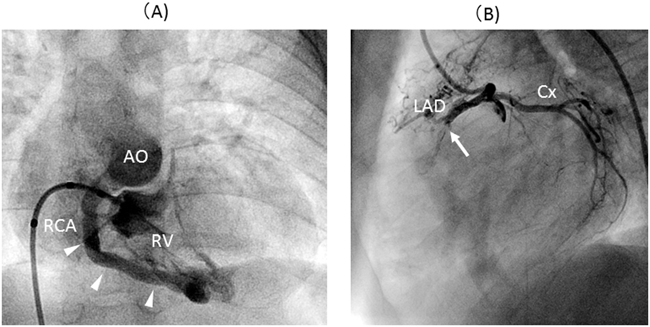

B) 右冠動脈左冠動脈洞起始(anomalous aortic origin of right coronary artery: AAORCA,またはR-ACAOS: right anomalous coronary arteries originating from the opposite sinus46)

右冠動脈が左冠動脈洞から鋭角に起始し,両大血管間を走行する異常を指す.AAOLCA-IAと同様に,開口部近位部の大動脈壁内走行を合併しやすい.Intravascular ultrasound(IVUS)等による観察では,壁内走行部位は側方から押される形でスリット状に狭窄しており,狭窄の程度は拍動性に変化し,収縮期に狭窄が最大となる.最狭窄部位は開口部近くの壁内走行近位部であり,狭窄率は面積比で平均50%(最大80%)であった50).本病態はAAOLCA-IAよりもリスクは低いと考えられているが,突然死を引き起こす可能性のある冠動脈異常の一つであり,malignant courseに分類される51)Fig. 5に15歳女児の自験例を示す.本症例は運動時胸痛を主訴に来院.経胸壁心エコー検査にて左冠動脈洞から起始した右冠動脈が両大血管間を走行しているのがカラードプラにて確認できる.AAOLCA-IAの症例と同様に,カラードプラにより両大血管間の異常な血流信号を丹念に評価することが本疾患の発見につながる.

Pediatric Cardiology and Cardiac Surgery 32(2): 95-113 (2016)

Fig. 5 Anomalous aortic origin of the right coronary artery

(A): Trans-thoracic echo: right coronary artery arises from left aortic sinus and runs the intramural course. Note the red-colored Doppler flow in the intramural course (white arrowheads).(B): Enhanced CT: right coronary artery arises from the left aortic sinus at an acute angle and courses intramurally and interarterially (black arrowheads).(C): Three-dimensional CT.L: left aortic sinus; NF: non-facing sinus; R: right aortic sinus.